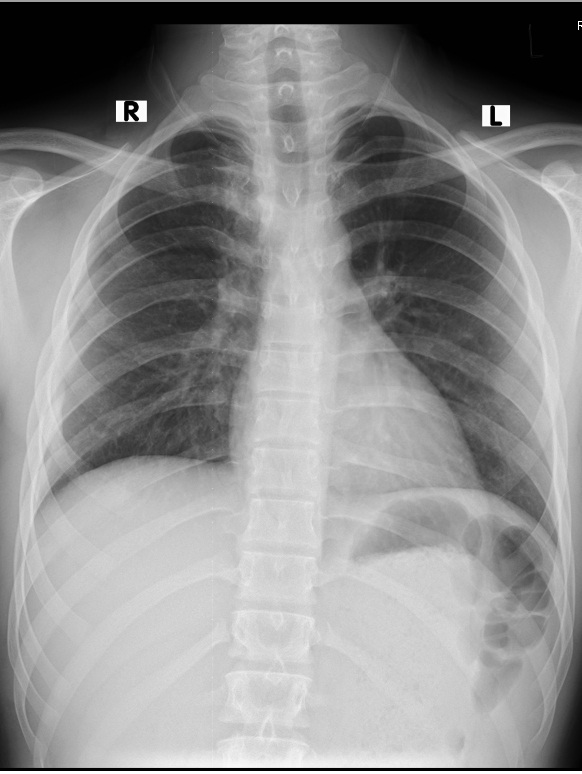

Figure 1. Chest x-ray (PA) showing a round opacity in the right mediastinum.

A 16-year-old boy presented with chest pain for the previous seven days that was more on the right side, gradual in onset, dull in character, intermittent, and radiating to the back. It was aggravated on exertion and was relieved with rest. The pain was associated with shortness of breath. The patient also complained of dysphagia, which was occasional and progressive. There was no history of cough or recent chest infection. General physical and systemic examinations were unremarkable. He had a low-grade fever with a hemoglobin of 13.5 g/dl, white cell count of 12.4/dL, and ESR of 52. Other routine lab investigations were within normal limits. His chest x-ray showed a right mediastinal round opacity on the right side of the carina. On his CECT scan Chest, the authors found a well-marginated nonenhancing thick fluid-attenuating lesion centered at the right paratracheal location in the middle and posterior mediastinum on the right side that was pressing on the esophagus and trachea.